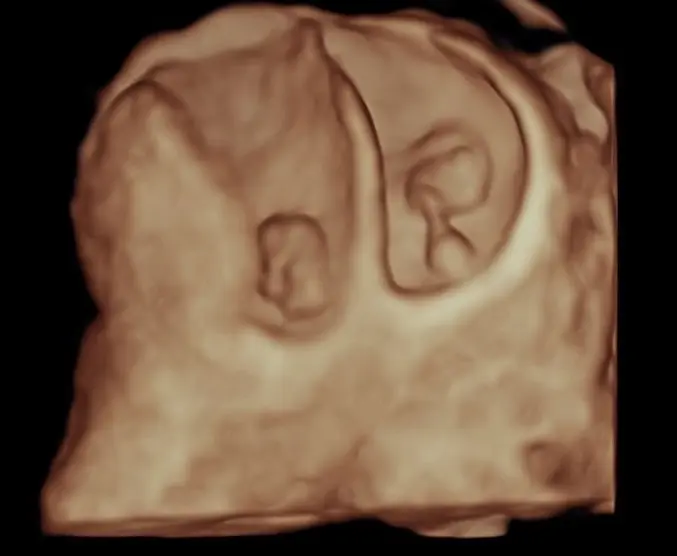

We connect to each other through our shared lived experiences. And pregnancy and birth are amongst the powerful experiences we can ever have. Utilising imaging technology enhances our own experiences further and also allows to share with our loved ones. Whilst we aim to capture great 3D images of your little one at every regular ultrasound, we also offer a dedicated ultrasound for bonding with your baby.

A 3D baby bonding ultrasound is a special type of non-medical ultrasound designed to give expectant parents a more detailed and lifelike view of their baby during pregnancy. Unlike standard diagnostic ultrasounds, which are used to assess your baby’s health and development, a 3D bonding scan focuses on creating clear, three-dimensional images that highlight your baby’s facial features, movements, and expressions in the womb. These ultrasounds are usually performed between 26 and 32 weeks of pregnancy, when there is enough fat under the baby’s skin to see the face clearly, but still enough amniotic fluid to produce quality images.